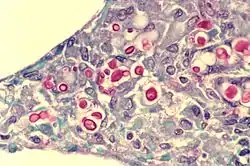

C. neoformans seen in the lung of a patient with AIDS. Mucicarmine stain is used in this case, staining the inner capsule of the organism red.

Cryptococcus neoformans typically grows as a yeast (unicellular) and replicates by budding. It makes hyphae during mating, and eventually creates basidiospores at the end of the hyphae before producing spores. Under host-relevant conditions, including low glucose, serum, 5% carbon dioxide, and low iron, among others, the cells produce a characteristic polysaccharide capsule.[6] The recognition of C. neoformans in Gram-stained smears of purulent exudates may be hampered by the presence of the large gelatinous capsule which apparently prevents definitive staining of the yeast-like cells. In such stained preparations, it may appear either as round cells with Gram-positive granular inclusions impressed upon a pale lavender cytoplasmic background or as Gram-negative lipoid bodies.[7] When grown as a yeast, C. neoformans has a prominent capsule composed mostly of polysaccharides. Under the microscope, the India ink stain is used for easy visualization of the capsule in cerebral spinal fluid.[8] The particles of ink pigment do not enter the capsule that surrounds the spherical yeast cell, resulting in a zone of clearance or "halo" around the cells. This allows for quick and easy identification of C. neoformans. Unusual morphological forms are rarely seen.[9] For identification in tissue, mucicarmine stain provides specific staining of polysaccharide cell wall in C. neoformans. Cryptococcal antigen from cerebrospinal fluid is thought to be the best test for diagnosis of cryptococcal meningitis in terms of sensitivity, though it might be unreliable in HIV-positive patients.[10]